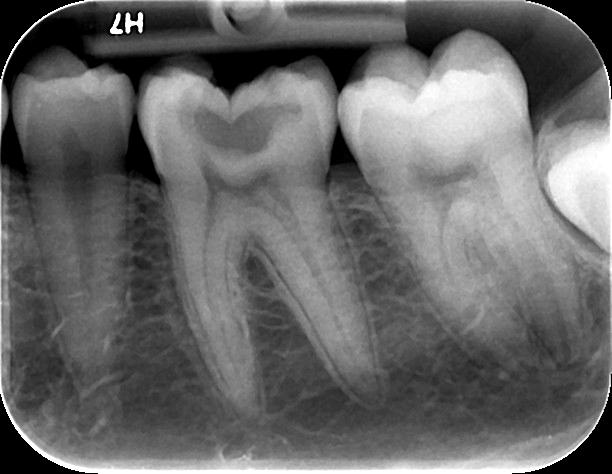

Η οπισθοφατνιακή ακτινογραφία λαμβάνεται με την τοποθέτηση του ακτινογραφικού πλακιδίου εσωτερικά των δοντιών (προς την πλευρά της γλώσσας ή του ουρανίσκου) και παράλληλα με αυτά. Χρησιμοποιείται ειδικός συγκρατητήρας του φιλμ, τον οποίο δαγκώνει ο εξεταζόμενος. Με αυτή απεικονίζονται ένα ή περισσότερα δόντια (τόσο η μύλη, όσο και η ρίζα αυτών), καθώς και τμήμα του φατνιακού οστού που περιβάλλει τις ρίζες των δοντιών. Αποτελεί την πιο απλή οδοντιατρική ακτινογραφική απεικόνιση. Χρησιμοποιούνται τρία μεγέθη φιλμ ή πλακιδίου ανάλογα με την περιοχή που θέλουμε να απεικονιστεί, το μέγεθος του στόματος του εξεταζόμενου και την ηλικία του. Η λήψη της είναι γρήγορη (διαρκεί λίγα δευτερόλεπτα) και ανώδυνη.

Η οπισθοφατνιακή ακτινογραφία μεταξύ άλλων μας επιτρέπει:

• την ανίχνευση οδοντικών τερηδόνων, τον καθορισμό της έκτασης και του βάθους τους και της σχέσης τους με τον πολφό του δοντιού

• τη μελέτη των ριζών των δοντιών (αριθμός, μορφολογία και πιθανή κάμψη αυτών, ύπαρξη απορρόφησης ή κατάγματος)

• τη μελέτη του αριθμού, της μορφολογίας, του εύρους και της πορείας των ριζικών σωλήνων εντός των ριζών

• τη μελέτη των σκληρών ιστών του περιοδοντίου, δηλαδή του φατνιακού οστού που περιβάλλει και στηρίζει το δόντι και του περιοδοντικού συνδέσμου. Σε περίπτωση περιοδοντικής νόσου, καθορίζεται η εντόπιση, ο βαθμός και η φύση (οριζόντια, γωνιώδης) της απορρόφησης του φατνιακού οστού

• τη μελέτη του φατνιακού οστού της περιακρορριζικής περιοχής του δοντιού για ύπαρξη παθολογικών εξεργασιών (απόστημα, κοκκίωμα, κύστη κ.λ.π.)

• την ανίχνευση κατάγματος των δοντιών.